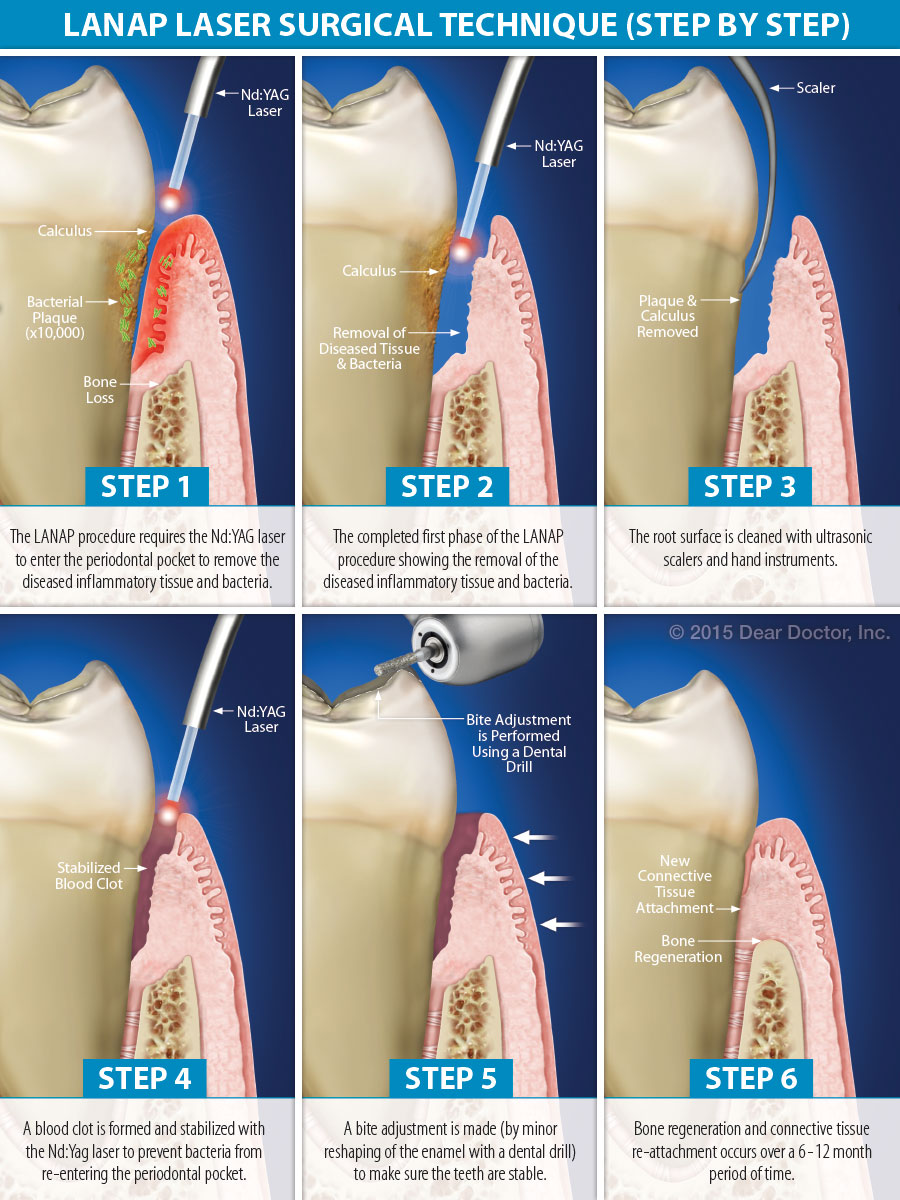

Lanap (Laser Gum Treatment)

라넵 레이저 치주염 치료

LANAP는 기존의 잇몸 수술에 비해 덜 고통스럽고 성공적인 치료를 제공하는 FDA 승인 레이저 잇몸 치료입니다. LANAP는 진정한 잇몸 재생, 새로운 뼈 성장 및 잇몸 조직 재 부착을 가져올 수있는 과학적으로 입증 된 방법론입니다.

LANAP 치료는 건강한 잇몸 조직을 손상 시키거나 제거하지 않고 염증의 원인을 표적으로 삼고, 부착 손실을 늦추거나 중단하고, 주머니 깊이를 줄이며, 잇몸 질환에서 회복 될 수 있도록하기 때문에 잇몸 질환 치료에서 가장 성공적인 프로토콜 중 하나입니다. 메스 나 봉합사가 필요없는 만성 감염, 치주염 치료에 탁월합니다.

기존에 치주염 치료방벙과 비교했을시 잇몸을 자르지 않아 아프지도 않고 수술후 잇몸이 더 내려 가지도 않는다는 장점이 있고 잇몸을 열고 하는 수술이랑 비교 했을때 수술후 결과가 훨씬 더 성공적입니다.